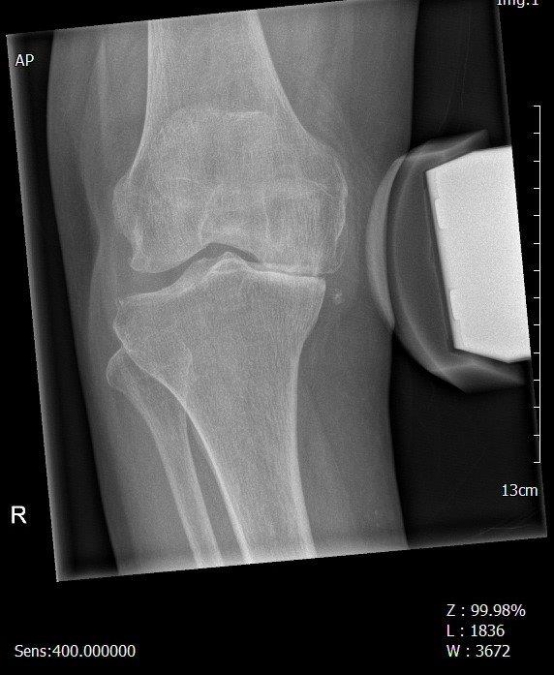

KNIEHALBGELENK - SCHLITTENPROTHESEN

In bis zu 20 -30 % der Fälle kommt es nur zu einer einseitigen, meist innenseitigen Abnutzung des Kniegelenkes. Die Außenseite des Gelenkes zeigt sich noch in einem guten Zustand. Oft sind mit diesem Verschleißmuster O-Beinachsenabweichungen verbunden. Die Verwendung von künstlichen Halbgelenken ermöglicht es, den noch gut erhaltenen Kniebereich zu erhalten. Die Funktion des Kniegelenkes mit den eigenen Kreuzbändern ist dabei besonders gut.

innenseitige Kniegelenksarthrose

OP Planung